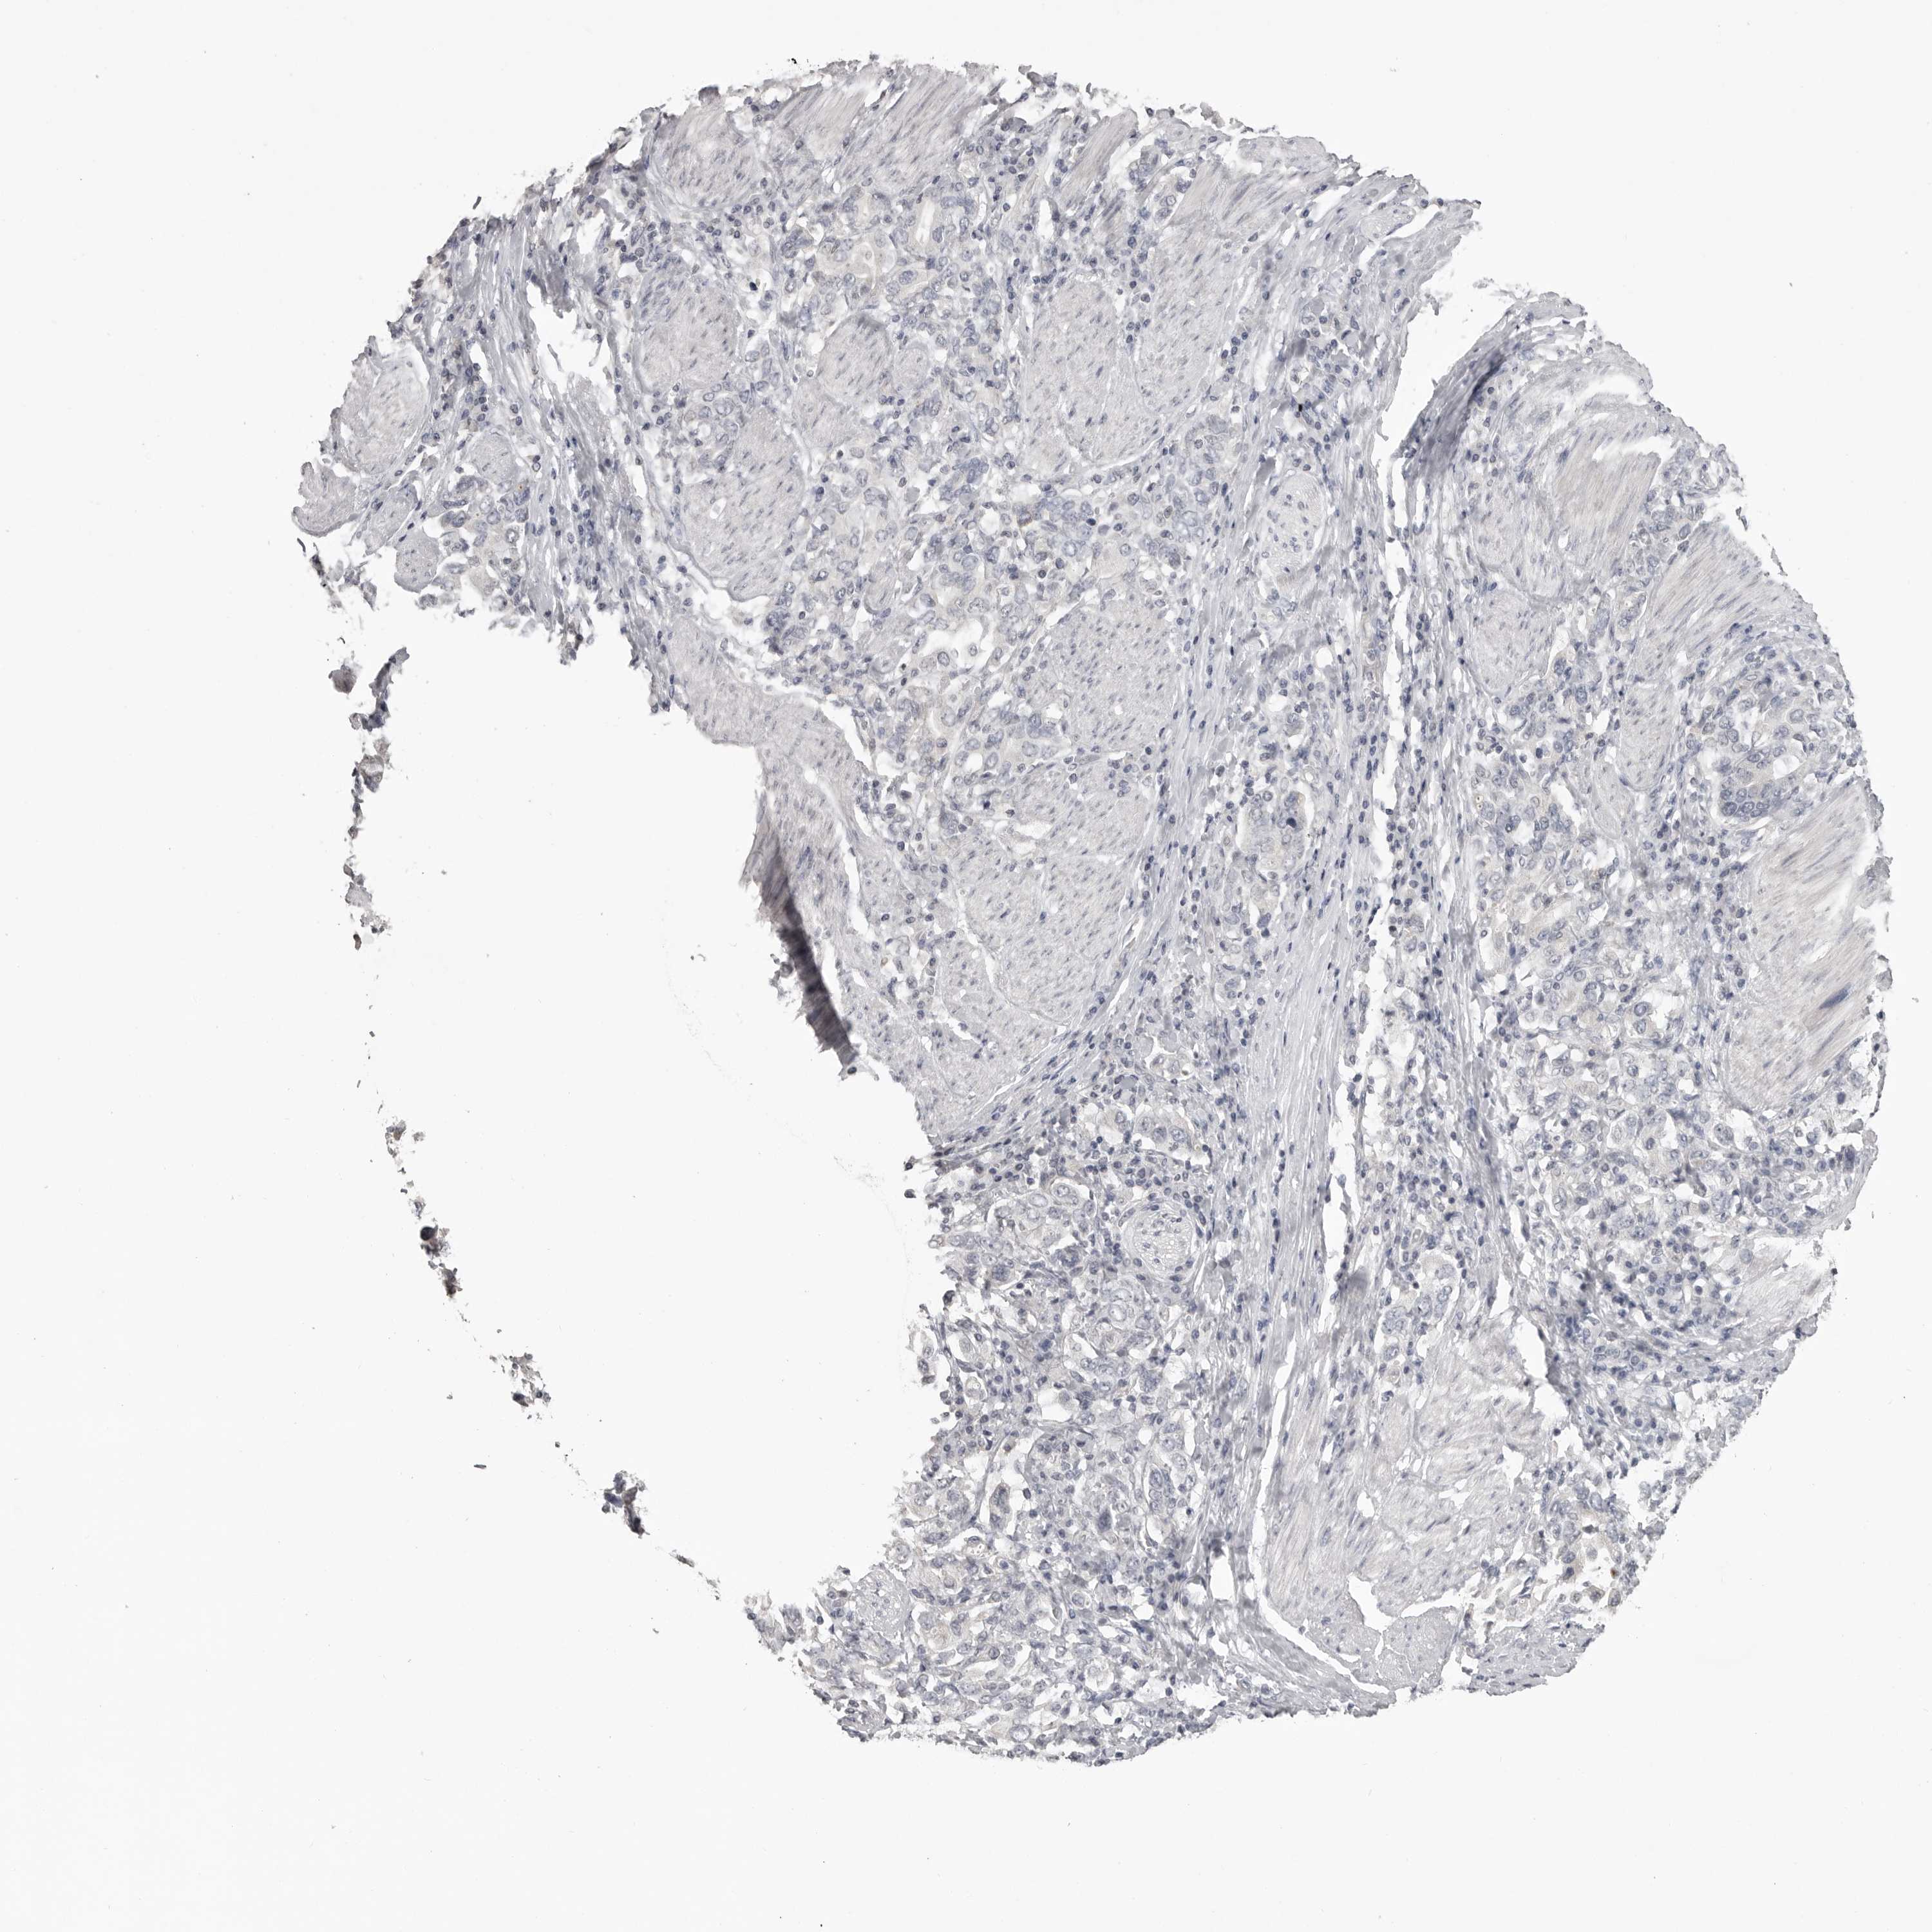

STOMACH CANCER - Protein expressioni

A mouse-over function shows sample information and annotation data. Click on an image to view it in a full screen mode. Samples can be filtered based on level of antibody staining by selecting one or several of the following categories: high, medium, low and not detected. The assay and annotation is described here.

Antibody stainingi

Antibody staining in the annotated cell types in the current human tissue is reported as not detected, low, medium, or high, based on conventional immunohistochemistry profiling in selected tissues. This score is based on the combination of the staining intensity and fraction of stained cells.

Each image is clickable and will lead to virtual microscopy that enables deeper exploration of all samples and also displays staining intensity scores, fraction scores and subcellular localization as well as patient and tissue information for each sample.

Antibody HPA028059

Staining

High

Medium

Low

Not detected

Intensity

Strong

Moderate

Weak

Negative

Quantity

>75%

75%-25%

<25%

None

Location

Nuclear

Cytoplasmic/membranous

Cytoplasmic/membranous,nuclear

Adenocarcinoma, NOS